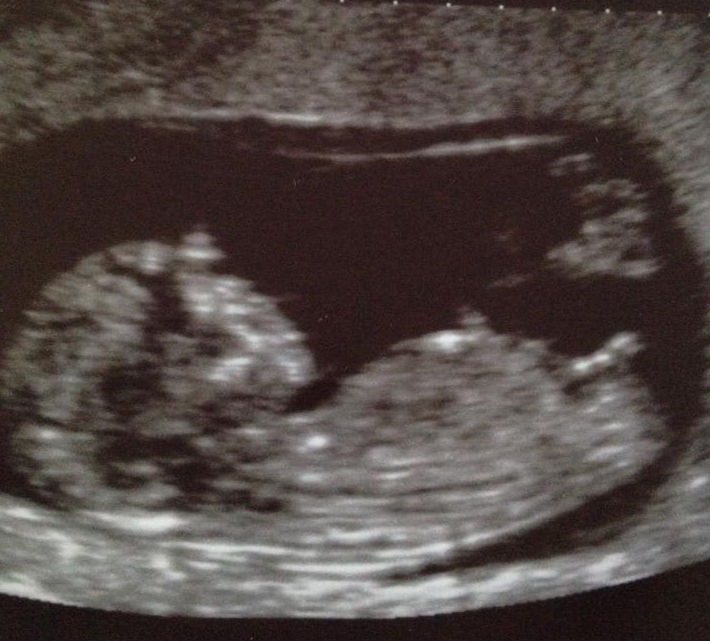

So what do you think? boy or girl

Scan was at 12+3

That one is tough depending on when it was I give it a slight girl lean but could be on its way up if scan was 12 weeks.

It looks pretty long and straight. :DD:

Slight girl lean....